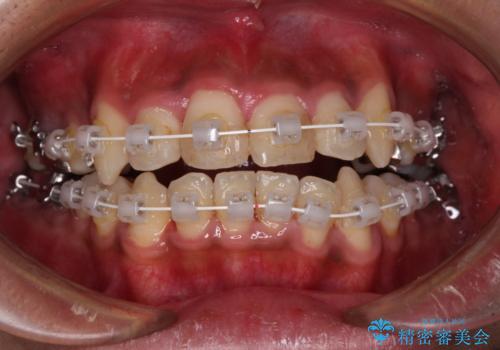

八重歯と開咬 ワイヤー装置での抜歯矯正

- 審美装置

- 前歯のデコボコと八重歯、開咬を気にして来院された患者様です。

骨格的に下顎骨が上顎骨に対して後退位であったため、上顎の左右第一小臼歯を抜歯し、デコボコを改善するとともに開咬を改善していくこととしました。

自己管理が煩わしいとのことで、表側のワイヤー装置にて治療を進めて行くこととしました。

舌の突出癖により開咬となっていたため、突出癖改善のためのトレーニングをしっかりと行っていただき、予定の期間で無事に治療を終えることができました。